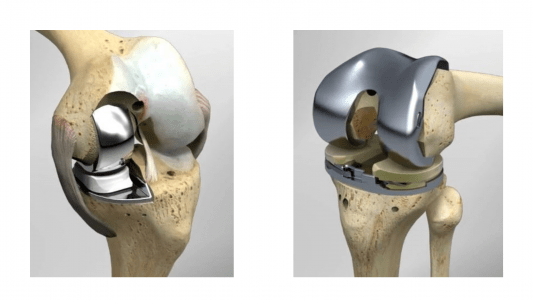

Μια εντελώς διαφορετική και πρωτοπόρα προσέγγιση στην χειρουργική αντιμετώπιση της οστεοαρθρίτιδας του γόνατος, με σημαντικά οφέλη για τον ασθενή, έρχεται να καθιερώσει η Κλινική «Κυανούς Σταυρός-Euromedica» Θεσσαλονίκης. Πρόκειται για την διαμερισματική αρθροπλαστική γόνατος, η οποία, σε αντίθεση με την συνήθη, ολική αρθροπλαστική, εστιάζει στην αντικατάσταση μόνον του φθαρμένου τμήματος της άρθρωσης (Εικόνα 1), χωρίς να θυσιάζονται τα υπόλοιπα υγιή τμήματα του γόνατος (Εικόνα 2).